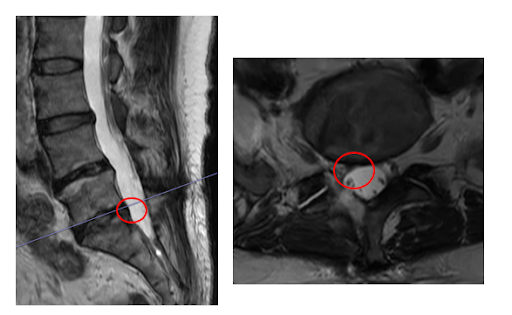

┃検査・診断

MRI検査を行い、赤い枠で示されている部分(L5/S)の椎間板ヘルニアと診断しました。

- PED(経皮的内視鏡下椎間板摘出術)

PED(経皮的内視鏡下椎間板摘出術)でヘルニアを切除し、神経の圧迫を取り除きました。手術直後の歩行にも、問題はありませんでした。